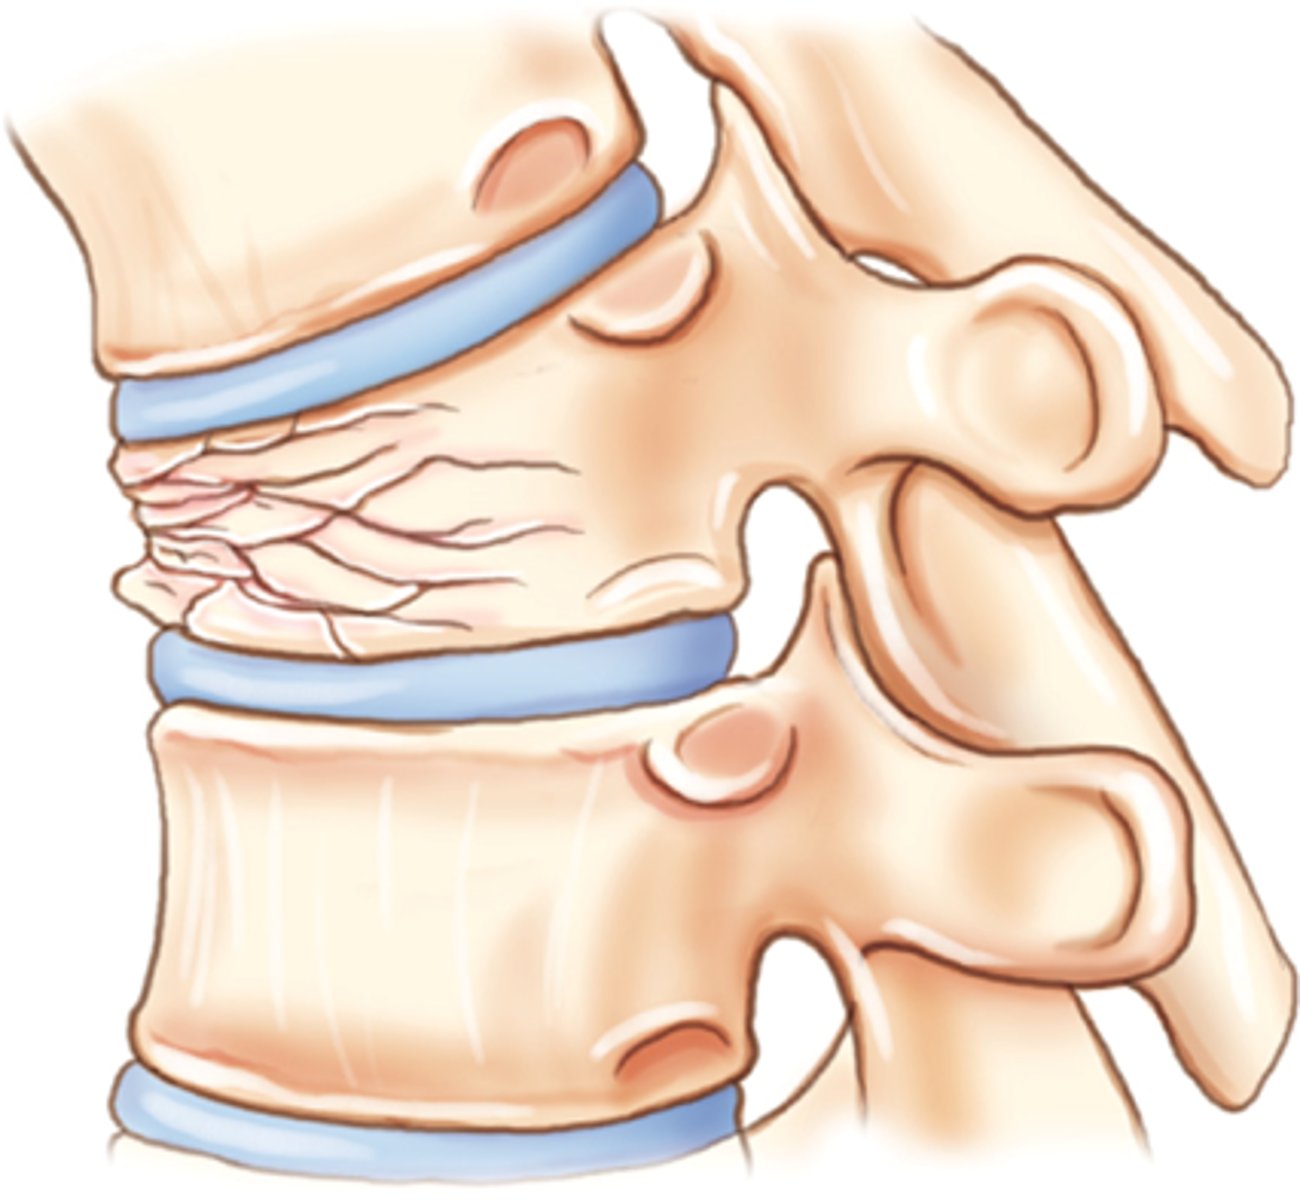

compression fracture

Crushed bone, causing wider/flatter appearance

vertebral fractures

where are compression fractures commonly seen